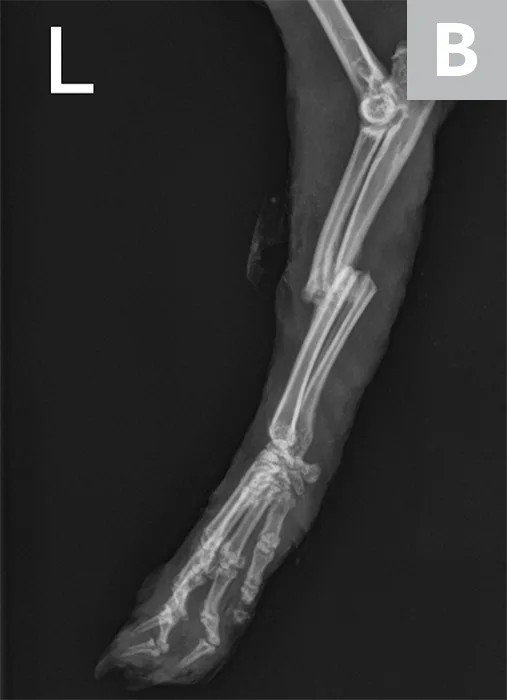

Right lateral radiograph of a 2-year-old male intact rabbit that caught his left front foot in a cage wire; parallel, mid-diaphyseal fractures of the radius and ulna can be seen (A). Due to financial constraints, the pet owners elected for external coaptation, which resulted in frequent splint failure (wet, too tight, pressure sores) that required 3 months of intensive care and resulted in suboptimal bone healing and near loss of the limb due to deep skin infections (B). Ideally, these fractures should have been treated surgically using a bone plate or an extra-skeletal fixation device.